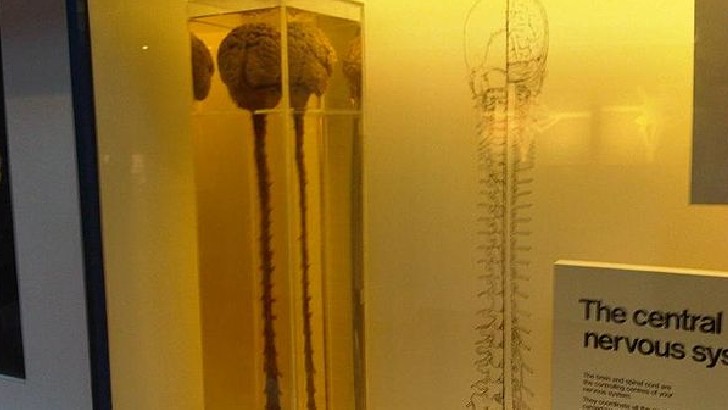

What causes multiple sclerosis symptoms?

Degeneration of the sheath that covers the neurons of the central system and the replacement of this sheath with scar tissue.

Excessive neurotransmitter release.

Multiple sclerosis is caused by obesity.

Excessive carbohydrate intake.

From the peripheral nervous system to the central nervous system, sensory neurons conduct impulses. Motor neurons transport signals from the central nervous system to muscles and glands. Between sensory and motor neurons, what kind of neurons are found?

Intraneurons

Ectoneurons

Interneurons

Paraneurons

Which of the following is the body’s single longest nerve?

Ulnar nerve

Sciatic nerve

Solar plexus

Radial nerve